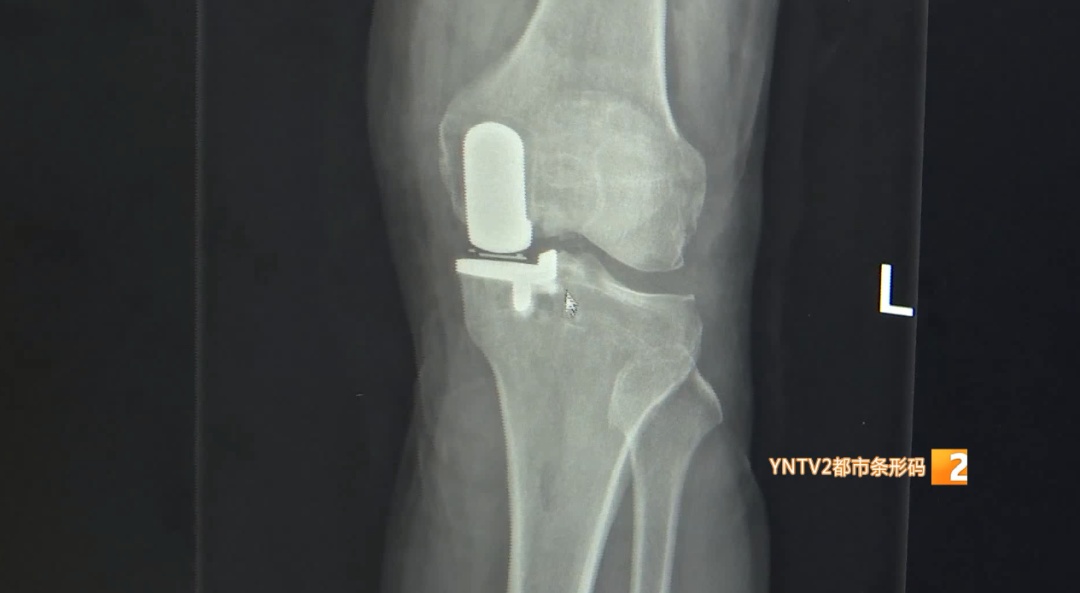

云南省第一人民医院骨科副主任医师 白云城:“初期的治疗包括休息,必要的止疼药物,还有康复理疗,到了中期,我们要考虑一定的手术方式,保护住膝关节正常的功能或者原有的功能,就是我们保膝大夫或者骨科大夫的初心和使命。”